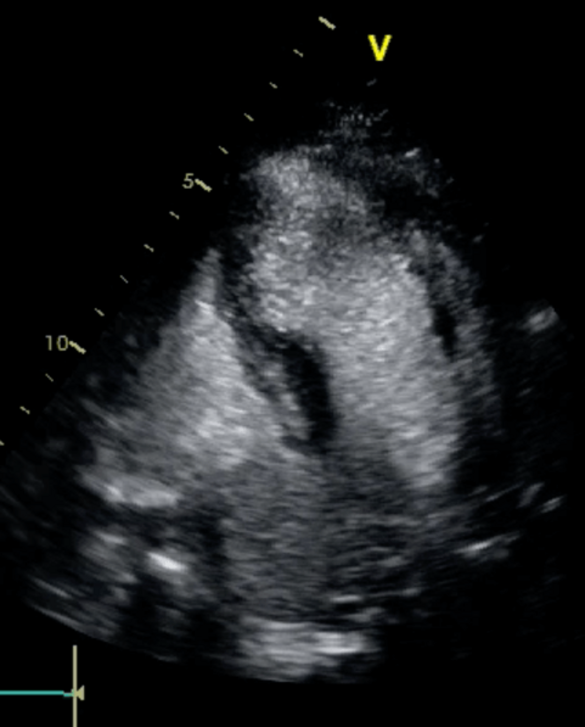

Der Herzultraschall (Echokardiographie) ist ein zentrales nicht-invasives Diagnostikum der modernen Kardiologie, um Patienten mit akuten oder chronischen Herzerkrankungen der richtigen Diagnosestellung und Therapie, wie auch der adäquaten Nachsorge zuführen zu können.

Die transthorakale Echokardiographie erfolgt als Ultraschalluntersuchung des Herzens über die Brustwand von außen. Eine Narkose ist nicht notwendig. Die Untersuchung ist, wie alle Ultraschalluntersuchungen, schmerzfrei.

Hier können Funktionsstörungen des Herzens, angeborene oder erworbene Herzerkrankungen inklusive Herzklappenauffälligkeiten unter Ruhebedingungen untersucht werden. Sie kommt als Routinediagnostik bei allen Herzerkrankungen (ob angeboren oder erworben) zum Einsatz.

Unter Standardbedingungen erfolgt die Untersuchung meist in Linksseitenlage auf einer Untersuchungsliege. Die moderne Ultraschalltechnik ermöglicht neben der 2 D-Darstellung des Herzens im bewegten Graustufenbild und der farblichen Darstellung des Blutflusses auch 3D-, und 4D- Darstellungen des Organs sowie komplexe Funktionsanalysen bei spezifischen Fragestellungen. Sie ermöglicht eine hervorragende Bildgebung und eine äußerst präzise Diagnostik.